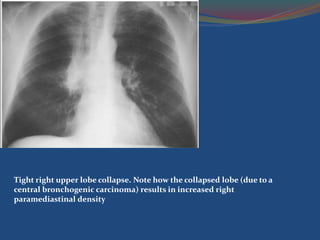

Right Upper Lobe Collapse

 Volume loss of the right upper lobe.

 Right upper zone has become dense due to lobar

collapse.

 The volume loss has displaced the trachea which

is PULLED to the right, and the horizontal fissure

(arrow) has been PULLED upwards

Tight right upper lobe collapse. Note how the collapsed lobe (due to a

central bronchogenic carcinoma) results in increased right

paramediastinal density